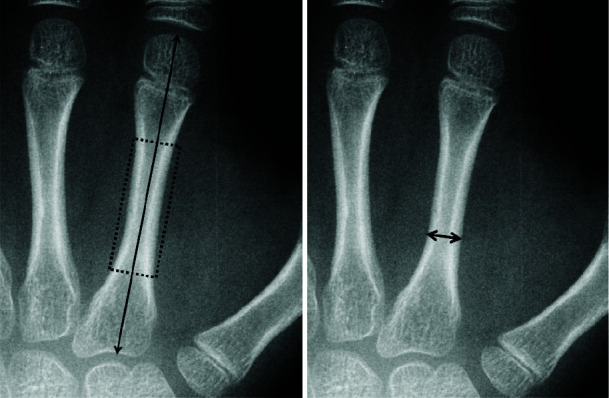

Statement of the problem: Bone age is a more accurate assessment for biologic development than chronological age. The most common method for bone age estimation is using Pyle and Greulich Atlas. Today, computer-based techniques are becoming more favorable among investigators. However, the morphological features in Greulich and Pyle method are difficult to be converted into quantitative measures. During recent years, metacarpal bones and metacarpophalangeal joints dimensions were shown to be highly correlated with skeletal age.

Purpose: In this study, we have evaluated the accuracy and reliability of a trained neural network for bone age estimation with quantitative and recently introduced related data, including chronological age, height, trunk height, weight, metacarpal bones, and metacarpophalangeal joints dimensions.